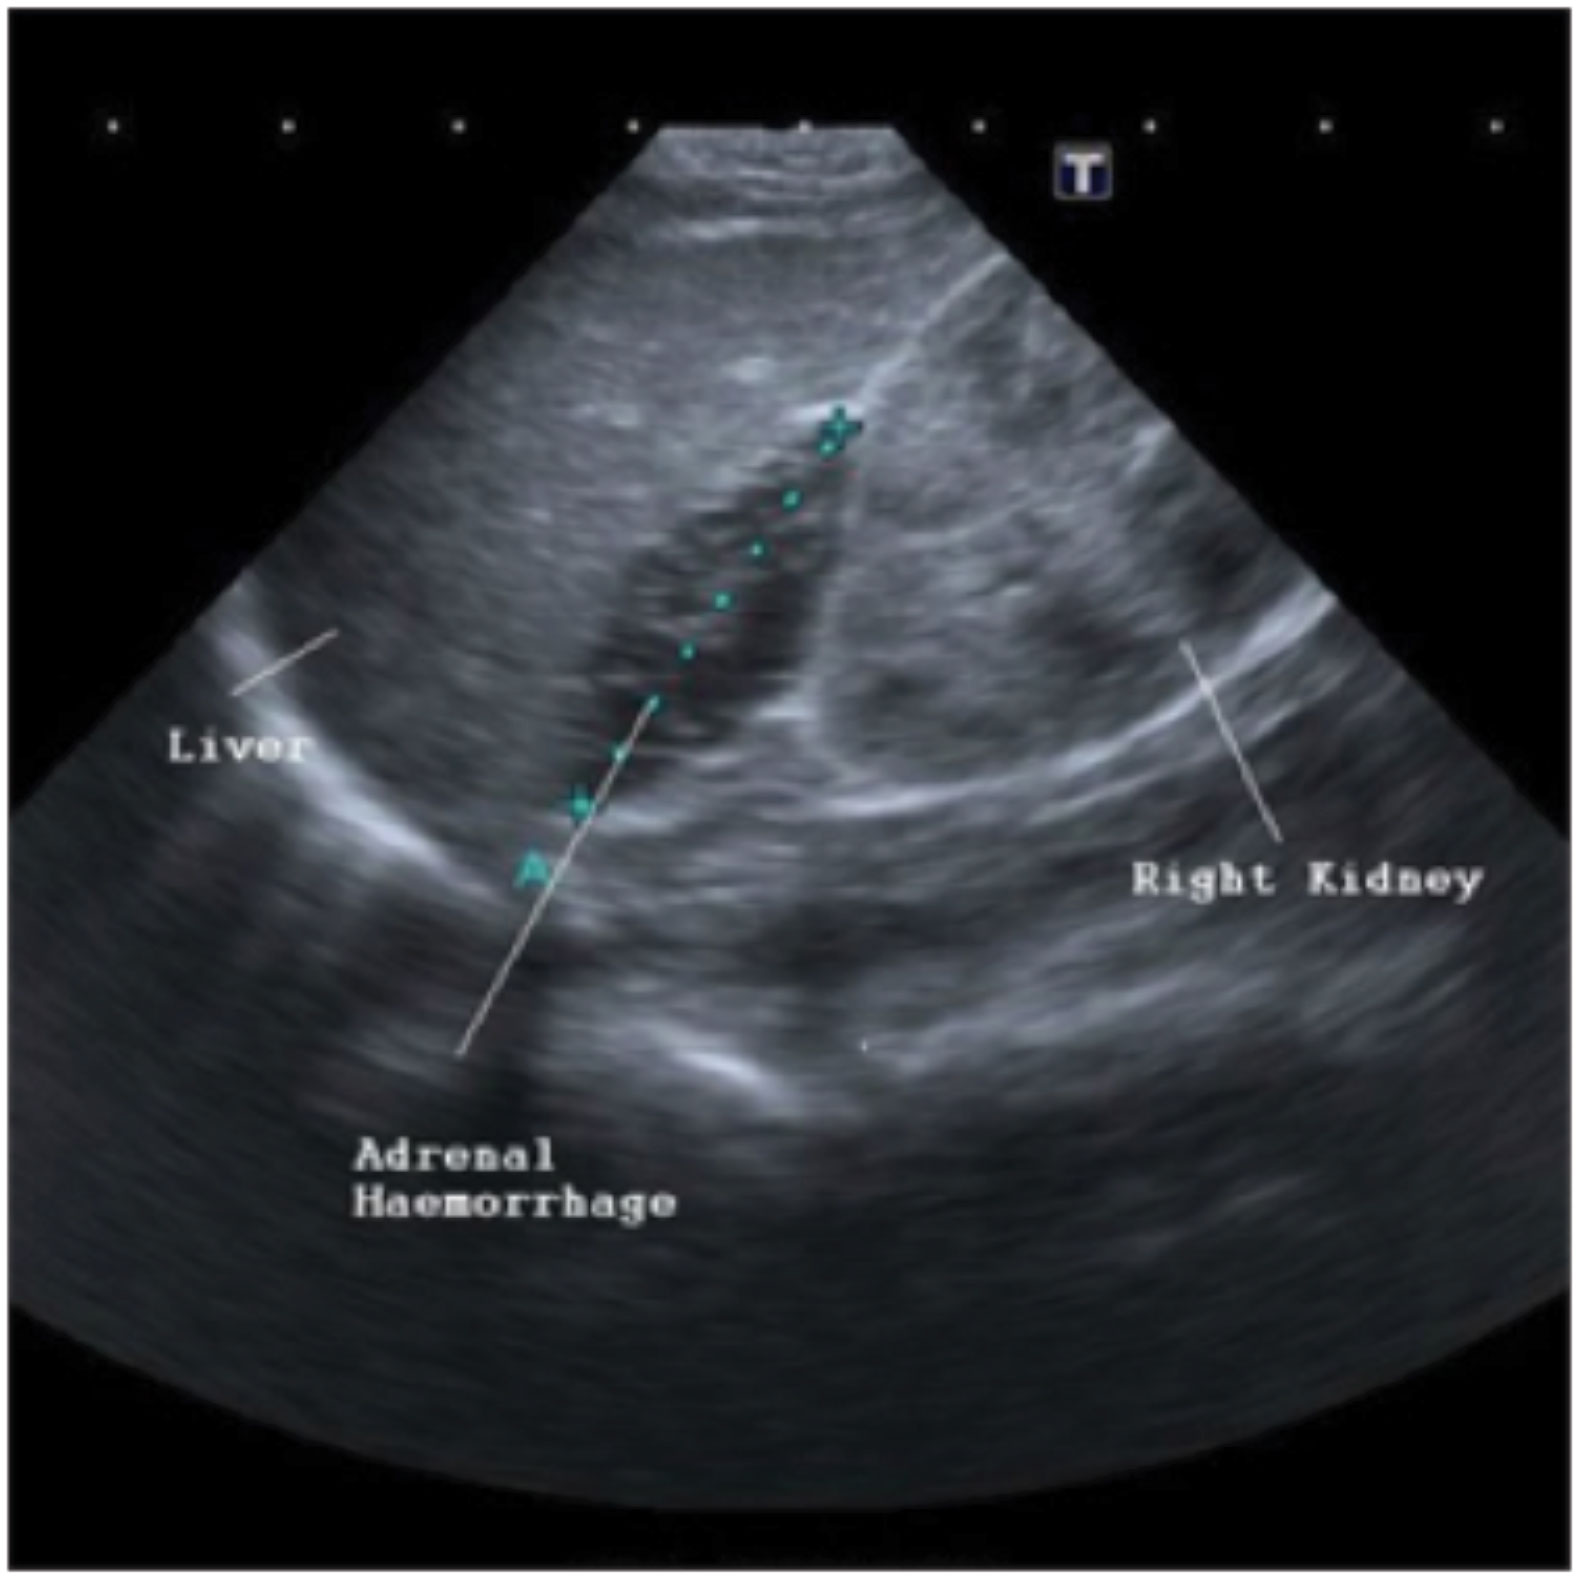

The infant had been born by normal delivery with no history of trauma or perinatal asphyxia and had remained in hospital from birth. Haemoglobin, platelets and coagulation studies were normal. An abdominal ultrasound identified a 3.1cm right-sided adrenal haemorrhage (see Figure 2)

(click to enlarge)